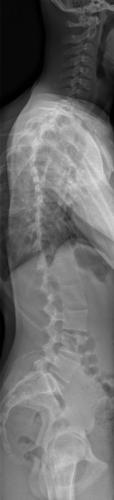

Images de scolioses opérées 16 janvier 202418 janvier 2023 par Damien Scoliose Thoracique 3 Scoliose thoracique D - Cliché pré-opératoire de Face Scoliose thoracique D - Cliché pré-opératoire de Profil Scoliose thoracique D - Cliché post-opératoire de Face Scoliose thoracique D - Cliché post-opératoire de Profil Aspect de la cicatrice à distance de l'intervention